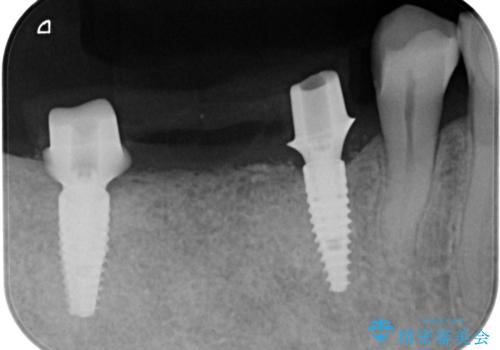

失った奥歯をインプラントで機能回復

- 3本失った奥歯の機能回復するために、インプラント治療を希望され来院されました。

よりしっかりと噛むことのできるインプラントによる治療を進めていくこととなりました。

- 110万円(インプラント×2・チタンカスタムアバットメント×2・ジルコニアクラウン×3・仮歯×3)費用は治療当時の料金となります